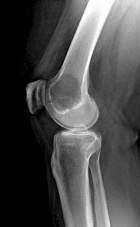

48 yo female w/ 3 mo h/o of R knee pain. Increasing w/o h/o trauma. C/o edema and pain with activity with mild alleviation with rest.

PE: RLE mod effusion about knee with pain at medial femoral condyle. No erythema. Painful ROM 0-130 at knee. No instability. NVI w/o LAN.